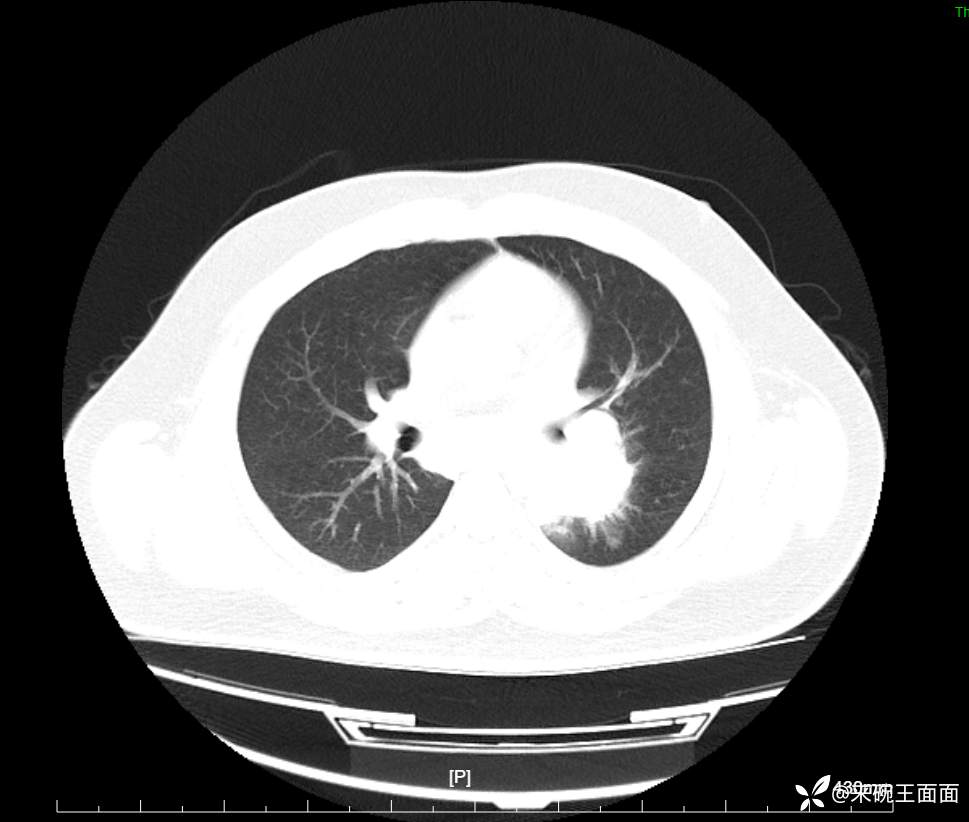

性别:男

年龄:27岁

主诉:胸闷胸痛数月余,休息后可自行缓解,无咯血症状。

个人史:数年吸烟史,具体不详。